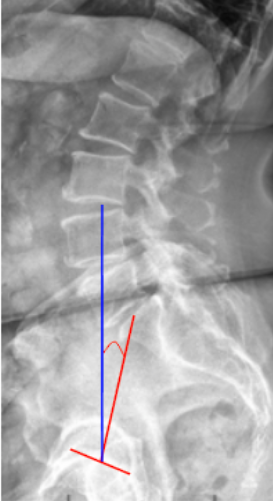

• Obtain a standing lateral lumbosacral X-ray with visualization of the femoral heads and sacrum.

• Identify two key anatomical landmarks:

• The center of the S1 endplate (midpoint of the superior sacral endplate).

• The center of the femoral heads (use the midpoint if both are visible).

• Draw a line connecting the center of the femoral heads to the center of the S1 endplate — this represents the pelvic axis.

• Draw a vertical reference line perpendicular to the horizontal plane.

• Measure the angle between the pelvic axis line and the vertical line — this is the Pelvic Tilt (PT).

• The angle opens posteriorly, increasing with pelvic retroversion.